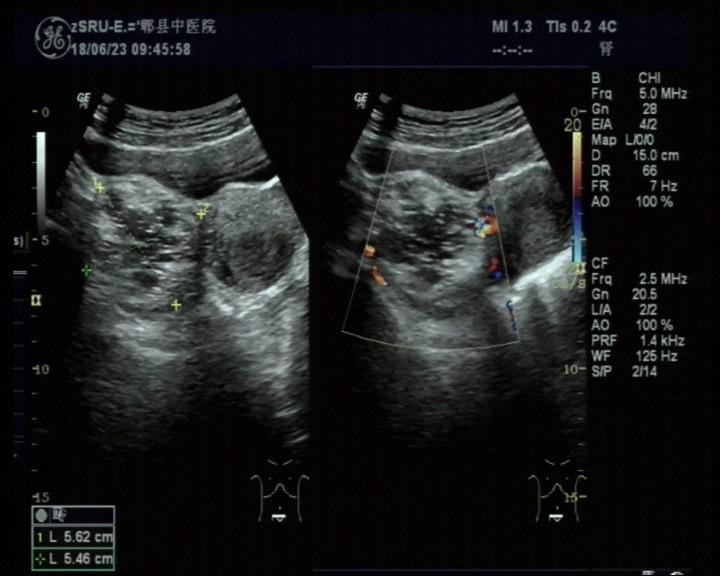

右侧附件区畸胎瘤可能

女,30岁,既往体检无异常,此次超声检查如图所示:右侧附件区探及一杂乱不均回声团,边界清楚,形态规则,CDFI:周边可见少许血流信号。